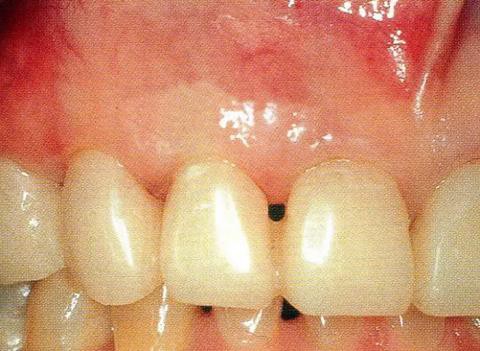

▼圖14-6 術(shù)后8個月的狀態(tài)。牙周探診值改善到了3mm,但出現(xiàn)了4mm的牙齦退縮。單獨使用EMD促生長因子時,根據(jù)骨缺損的類型可能會出現(xiàn)制造空間較困難,也可能會出現(xiàn)牙齦的凹陷。

▼圖14-7 術(shù)后9年的狀態(tài)。